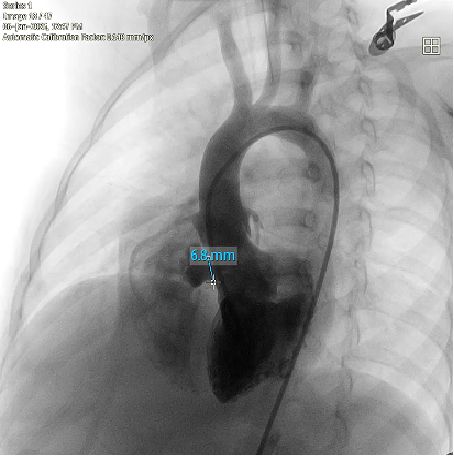

When faced with a complex congenital heart defect in a 2-year-old, how do we balance efficacy with lifelong safety? Meet a pediatric patient with a membranous ventricular septal defect (VSD) accompanied by pseudoaneurysm formation (basal width: 8.2 mm, shunt: 3.5 mm) and left ventricular false tendon—a rare and anatomically challenging scenario. Over two years of 5-time's follow-up, she was all diagnosed with typical membranous VSD, with a high-velocity left-to-right shunt (peak velocity: 5.1 m/s, gradient: 104 mmHg) and mild tricuspid regurgitation. Traditional metal occluders risk interfering with adjacent structures like the false tendon, potentially causing thromboembolism or valve dysfunction. But innovation stepped in: A memosorb fully biodegradable occluder was chosen. Why? 1.  Adaptive design: Conforms to complex VSD anatomy, ensuring stability. 2. Degrades over time: Eliminates long-term risks of metal implants. 3. Preserves future options: No permanent hardware for a growing child. This case highlights the power of patient-centered innovation in congenital heart disease. Collaboration between imaging experts, interventional cardiologists, and families is key to navigating these high-stakes decisions.